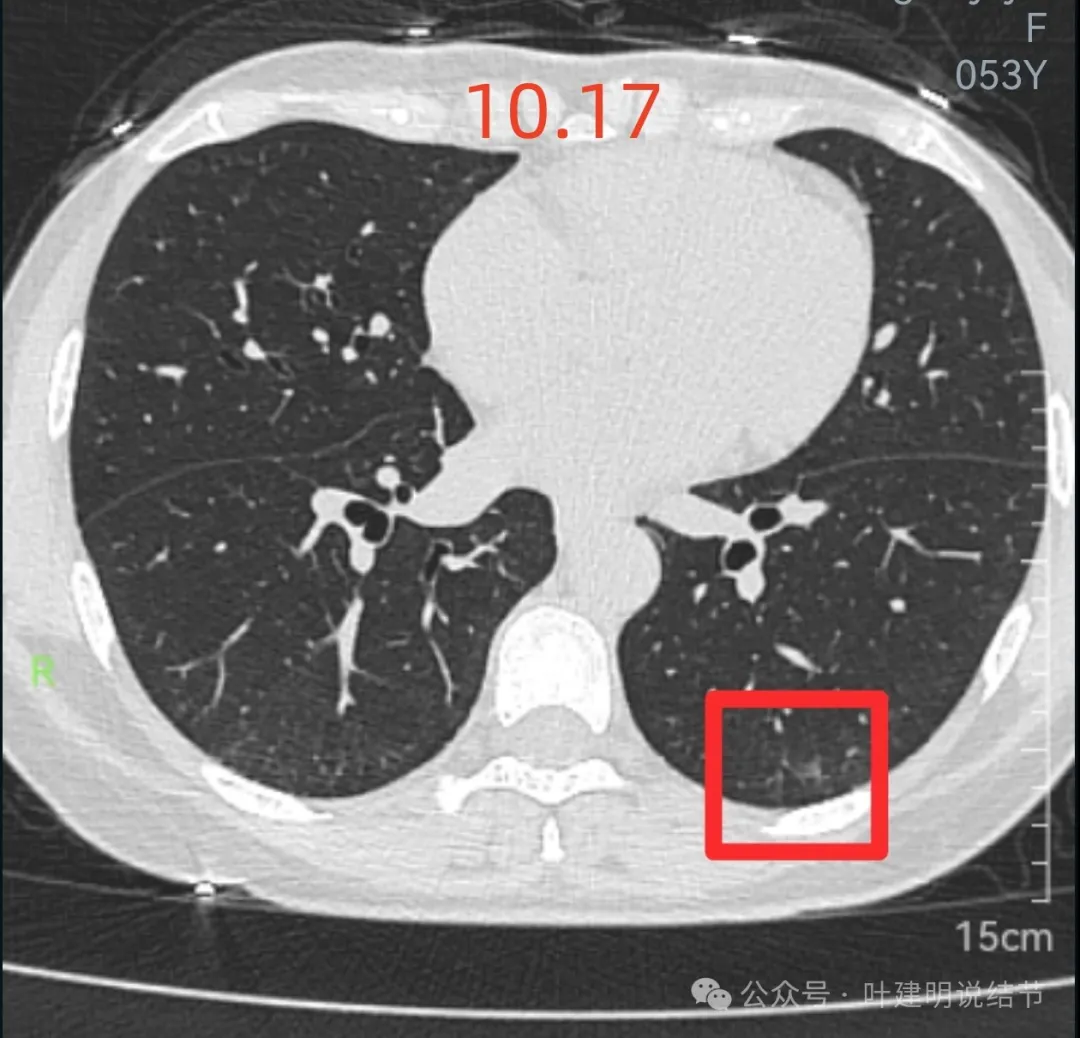

先来看2024年10月16日的影像:

右上后段混合密度结节,瘤肺边界欠清,有明显实性成分,边缘不光滑。

右肺很淡的磨玻璃阴影,伴进入的血管异常增粗,整体轮廓尚显清楚。

右下叶背段边界欠清的磨玻璃影,有血管刚好位于病灶处。

左下小片状模糊影,轮廓与边界欠清。

左下叶混合密度结节,边缘有淡的磨玻璃影,瘤肺边界欠清,实性成分明显,略偏散。

右下叶以及左下叶实性结节,缺乏膨胀性,没有收缩力,紧贴胸壁或膈肌无牵拉凹陷。

蓝色的是实性的小结节,缺乏膨胀性,两次检查都有,没有变化,考虑是良性的;红色的这些事10月份检查新增的,这两处比较明显的9月份的时候就是绿色框起来这个区域,当时是没有的。短时间内出现、多发病灶、边缘模糊、轮廓欠清,没有恶性特征,与炎性病变符合。建议查查隐球菌方面的化验,如此结果阳性,请呼吸内科或感染科处理。意见供参考!

再来看周教授认为4B类的右上后段病灶连续层面影像信息:

病灶出现,轮廓不清,瘤肺边界模糊,有血管穿行,血管有异常增粗。

血管壁有异常密度增高,病灶混合密度,轮廓总体在此层较清,但瘤肺边界不清。

病灶偏实性部分不密实,磨玻璃部分过淡且模糊。

边缘有毛刺,但不够锐利;外周磨玻璃成分密度过淡且界限不清;实性部分也显得不致密;与叶间裂距离近但没有任何牵拉影响。

实性成分在灶内看,也是界限不清,磨玻璃部分淡而糊。

整体感觉像病灶中间偏实性些的成分伴外周晕征。

边缘区域离叶间裂更近,仍无牵拉。

几乎贴着叶间裂了,仍无任何牵拉影响。

病灶密度边缘部分也不均,离叶间裂近而没有影响。

上图病灶已经贴着叶间裂,但仍显示是平直的,没有任何牵拉影响。

矢状位上看,病灶虽整体轮廓较清,但瘤肺边界显模糊,整体不致密。

冠状位上看病灶有实性成分,实性成分缺乏收缩力,外围是淡磨玻璃成分,瘤肺边界欠清,贴着叶裂没有影响。

从连续层面以及影像细节上看,这个病灶就不可能是恶性的!短期内出现,混合密度而瘤肺边界不清,整体缺乏收缩力也无膨胀性,灶内实性成分不致密且磨玻璃成分过淡,灶内血管有异常增粗与密度过高,又是两肺多发病灶。这所有的表现与病情发展都与感染性病变契合,周围淡磨就是炎症水肿的关系,血管异常就是管壁有炎症的关系,多发就是感染(致病因素)影响两肺的关系。怎么可能是恶性?